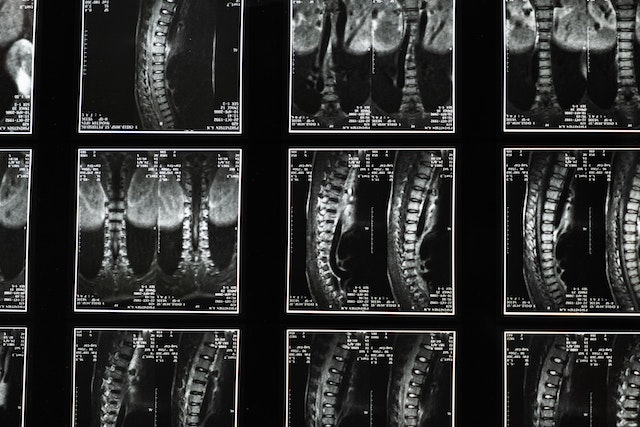

다음으로 X-레이 진단법이 있습니다. 이 방법은 보다 정확한 만곡각을 보여줍니다. 만곡은 정도는 척추를 X-레이로 촬영했을 때 두 선 사이의 각도로 알아볼 수 있습니다. 이 각도를 콥(Cobb) 각도라고 부릅니다

한 선은 가장 기울어진 위쪽 척추뼈의 상단으로부터 뻗어 나옵니다. 다른 한 선은 가장 기울어진 하부 척추뼈의 바닥에서 뻗어 나옵니다. 이렇게 뻗어 나온 선이 마주치는 곳에서 형성된 각도를 콥 각도라고 합니다

의사는 척추측만증이 악화될 수 있다고 판단되는 청소년에게 일 년에 여러 차례 검사를 받도록 안내할 수 있습니다. 척추 만곡을 좀 더 정확하게 측정하기 위해 특별한 장치가 사용될 수도 있습니다